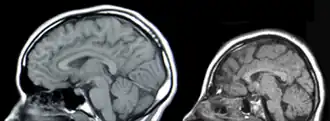

У́мственная отста́лость, ранее — малоу́мие, олигофрени́я (др.-греч. ὀλίγος «малый» + φρήν «ум») — врождённая или приобретённая в период развития задержка либо неполное развитие психики, проявляющаяся нарушением интеллекта, вызванная патологией головного мозга и ведущая к социальной дезадаптации[2]. Проявляется в первую очередь в отношении разума (откуда и название), также в отношении эмоций, воли, речи и моторики.

- F7x.x8 — …обусловленная другими уточнёнными причинами (например: врождённая аномалия головного мозга, краниосиностоз, микроцефалия, гипертелоризм и т. д.)